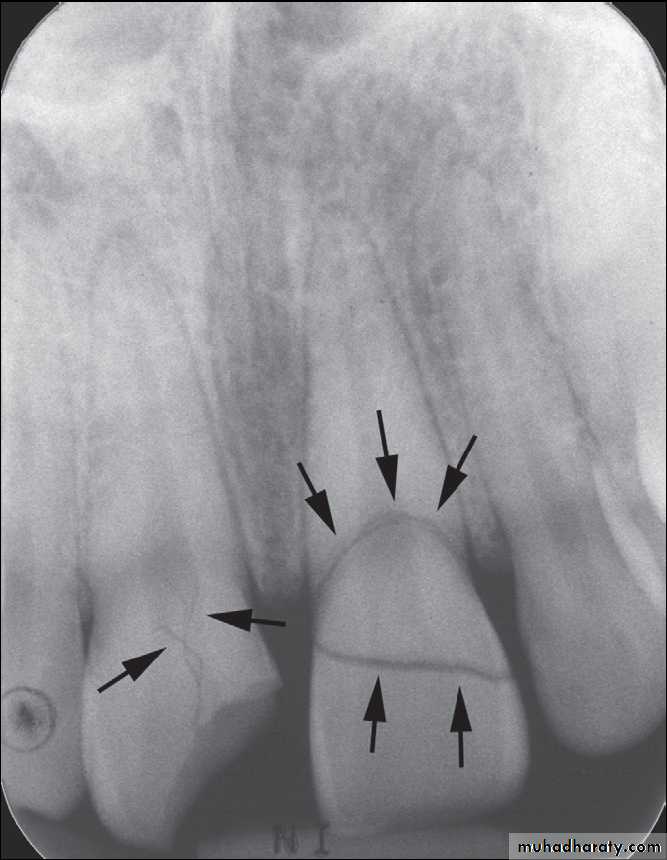

As far as radiographs are concerned, periapical and occlusal radiographs are best, with panoramic imaging slightly less favorable, especially with the anterior dentition.